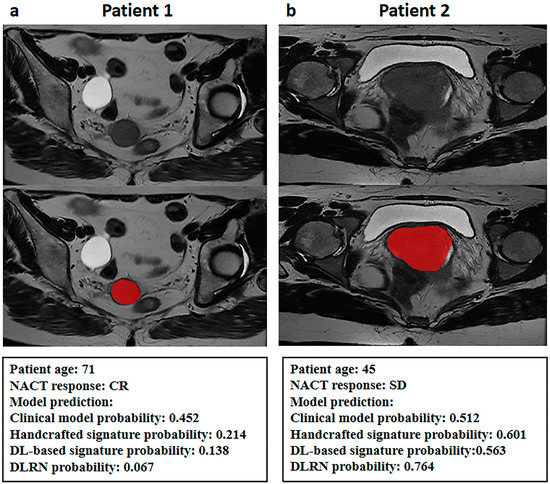

| Index | β | Odds Ratio (95% CI) | Multivariate p Value |

|---|---|---|---|

| Clinical model probability | 1.297 | 3.660 (1.109–12.082) | 0.033 * |

| Handcrafted radiomics signature probability | 1.087 | 2.965 (1.796–4.893) | <0.001 * |

| DL-based radiomics signature probability | 1.157 | 3.181 (1.845–5.486) | <0.001 * |

| Intercept | −0.547 | - | 0.078 |